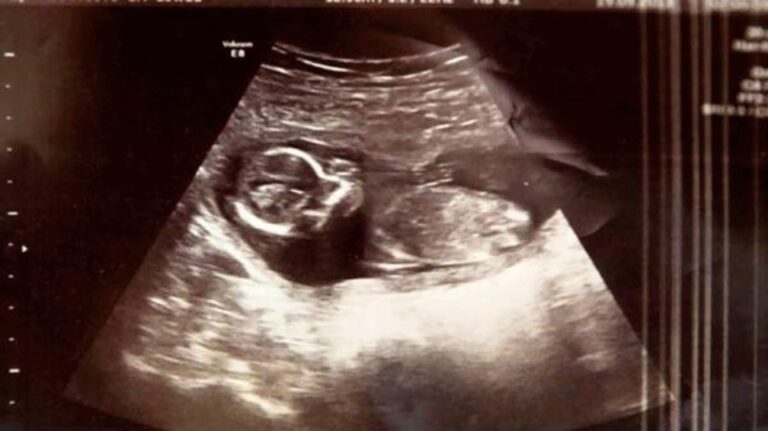

The result was positive and they decided to go back to the doctor to make sure everything was okay. The doctors told her to scrape the uterus to clean the uterus of the remaining tissue. Before scheduling the procedure, they did another ultrasound. The doctors’ surprise was huge! They found out that Michelle was indeed pregnant with twins and is still pregnant! It is a miracle that the baby was not affected after treatment with drugs to clean the uterus.

Michelle and Ross were delighted to learn that Michelle had a healthy baby in her womb. A little girl named Megan was born healthy and there were no complications! Michelle and Ross call Megan their ‘miracle’ because they fight back after the treatment! It’s so sad that her twin sister couldn’t survive, she will take care of the family for sure! The three adorable babies named Megan, Noah and Maya are the pride and joy of Michelle and Ross! Share this story with your loved ones!